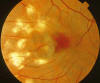

Fig. 1.

Retinografía del ojo derecho del paciente en la que llaman la atención las cicatrices coriorretinianas (histo-spots) y se intuye la fibrosis subretiniana fusiforme adyacente al centro de la fóvea.